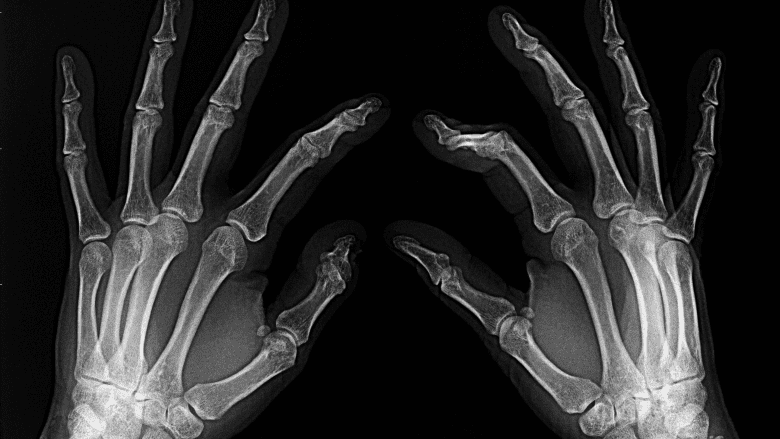

Hand arthritis is most likely to cause symptoms beginning in a person’s 50s or 60s.3Prieto-Alhambra D, Judge A, Javaid MK, Cooper C, Diez-Perez A, Arden NK. Incidence and risk factors for clinically diagnosed knee, hip and hand osteoarthritis: influences of age, gender and osteoarthritis affecting other joints. Ann Rheum Dis. 2014;73(9):1659‐1664. doi:10.1136/annrheumdis-2013-203355,4Marshall M, Watt FE, Vincent TL, Dziedzic K. Hand osteoarthritis: clinical phenotypes, molecular mechanisms and disease management. Nat Rev Rheumatol. 2018;14(11):641‐656. doi:10.1038/s41584-018-0095-4 Most adults over the age of 55 have signs of hand osteoarthritis that can be seen on X-rays,5Dahaghin S, Bierma-Zeinstra S, Ginai A, Pols H, Hazes J, Koes B. Prevalence and pattern of radiographic hand osteoarthritis and association with pain and disability (the Rotterdam study). Annals of the Rheumatic Diseases. 2005;64(5):682-687. doi:10.1136/ard.2004.023564. even though many do not experience pain and stiffness.